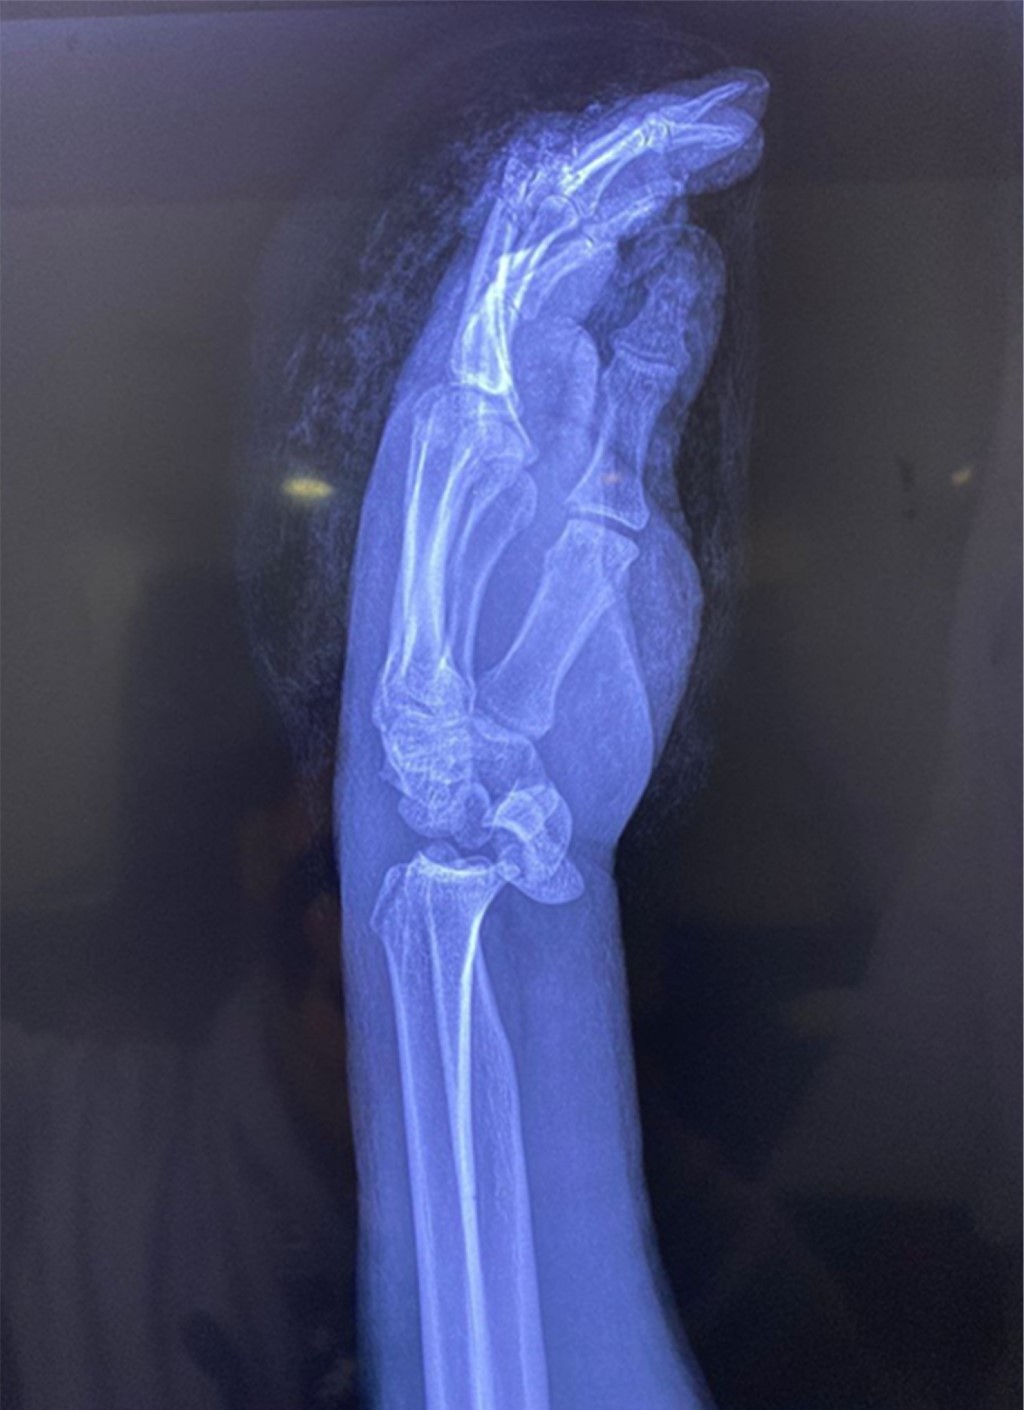

Paciente masculino de 48 años de edad, quien ingresa a nuestra unidad hospitalaria tras presentar lesión en mano izquierda posterior a carga axial, así como compresión al ser arrollado por vehículo automotor; a su ingreso, se identifica incongruencia articular en las líneas de Gilula (Figuras 1 y 2).

Además de presentar fractura en metáfisis proximal con extensión a metáfisis distal de F2 de tercer dedo, amputación traumática con desarticulación de F1-F2 más denudamiento de cuarto dedo, herida cruenta de quinto dedo más lesión del extensor propio del quinto dedo en zona V. A su ingreso pasa a cirugía de control de daños más reducción cerrada de luxación peri-escafo-transtrapecio-transtrapezoidea (Figura 3).